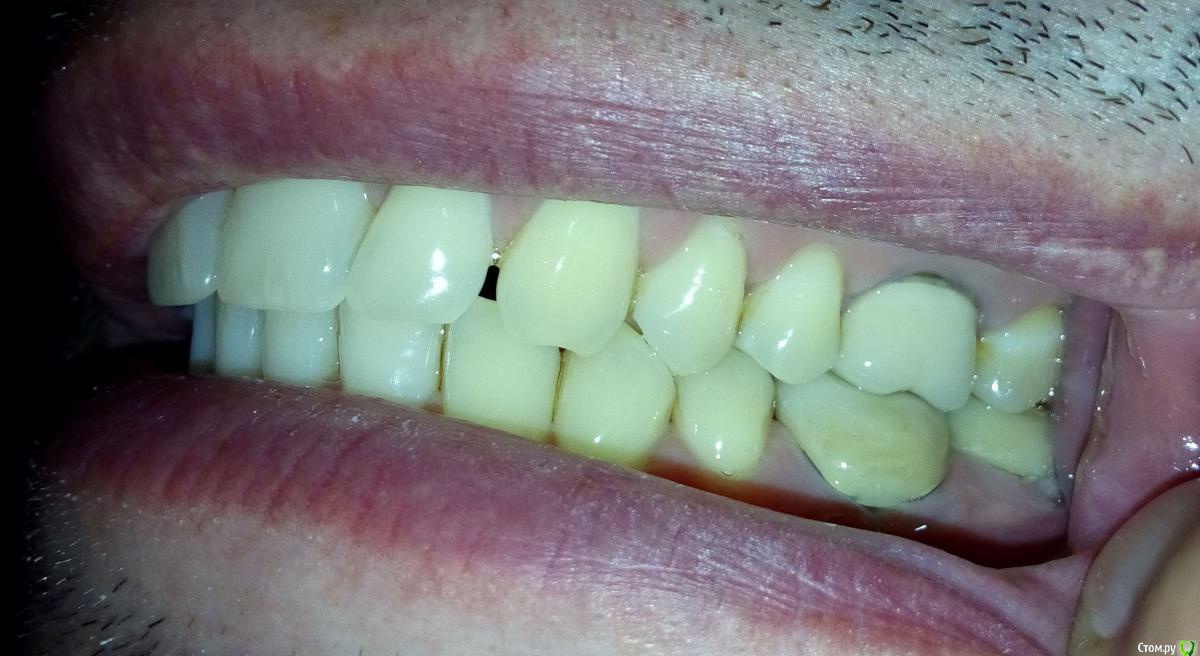

-судя по бугристости на углах нижней челюсти и фасеткам стираемости  на многих зубах , Вы- бруксист! и еще тот!)  отсюда и симптоматика, и боли в мышцах.

>>-судя по бугристости на углах нижней челюсти и фасеткам стираемости  на многих >>зубах , Вы- бруксист! и еще тот!)  отсюда и симптоматика, и боли в мышцах.

Дело в том, что жена (человек спящий со мной бок о бок более 10 лет) ни разу не отмечала скрежет во сне. По утрам никогда не болели мышцы. У меня обычно другая проблема -  могу спать с полуоткрытоым ртом так, что (простите за подробность) вытекают слюни и мокнет подушка :-)

Так же могу отметить, что форма старых 36 и 37 металлокерамичких коронок и старых зубов была плоскими (почти ровная площадка), стоматологи это свзязывали с тем, что зубы антагонисты соприкасались бугор-бугор, а не бугор-впадина. Самое инетерсное, что сейчас мне сделали бугры на коронке, которые попадают в впадины, но этот доцент, не зная какими были ранее зубы и коронки, констатировала, что ранее они были плоскими. Может стОит вернуться к старым формам? :wacko: